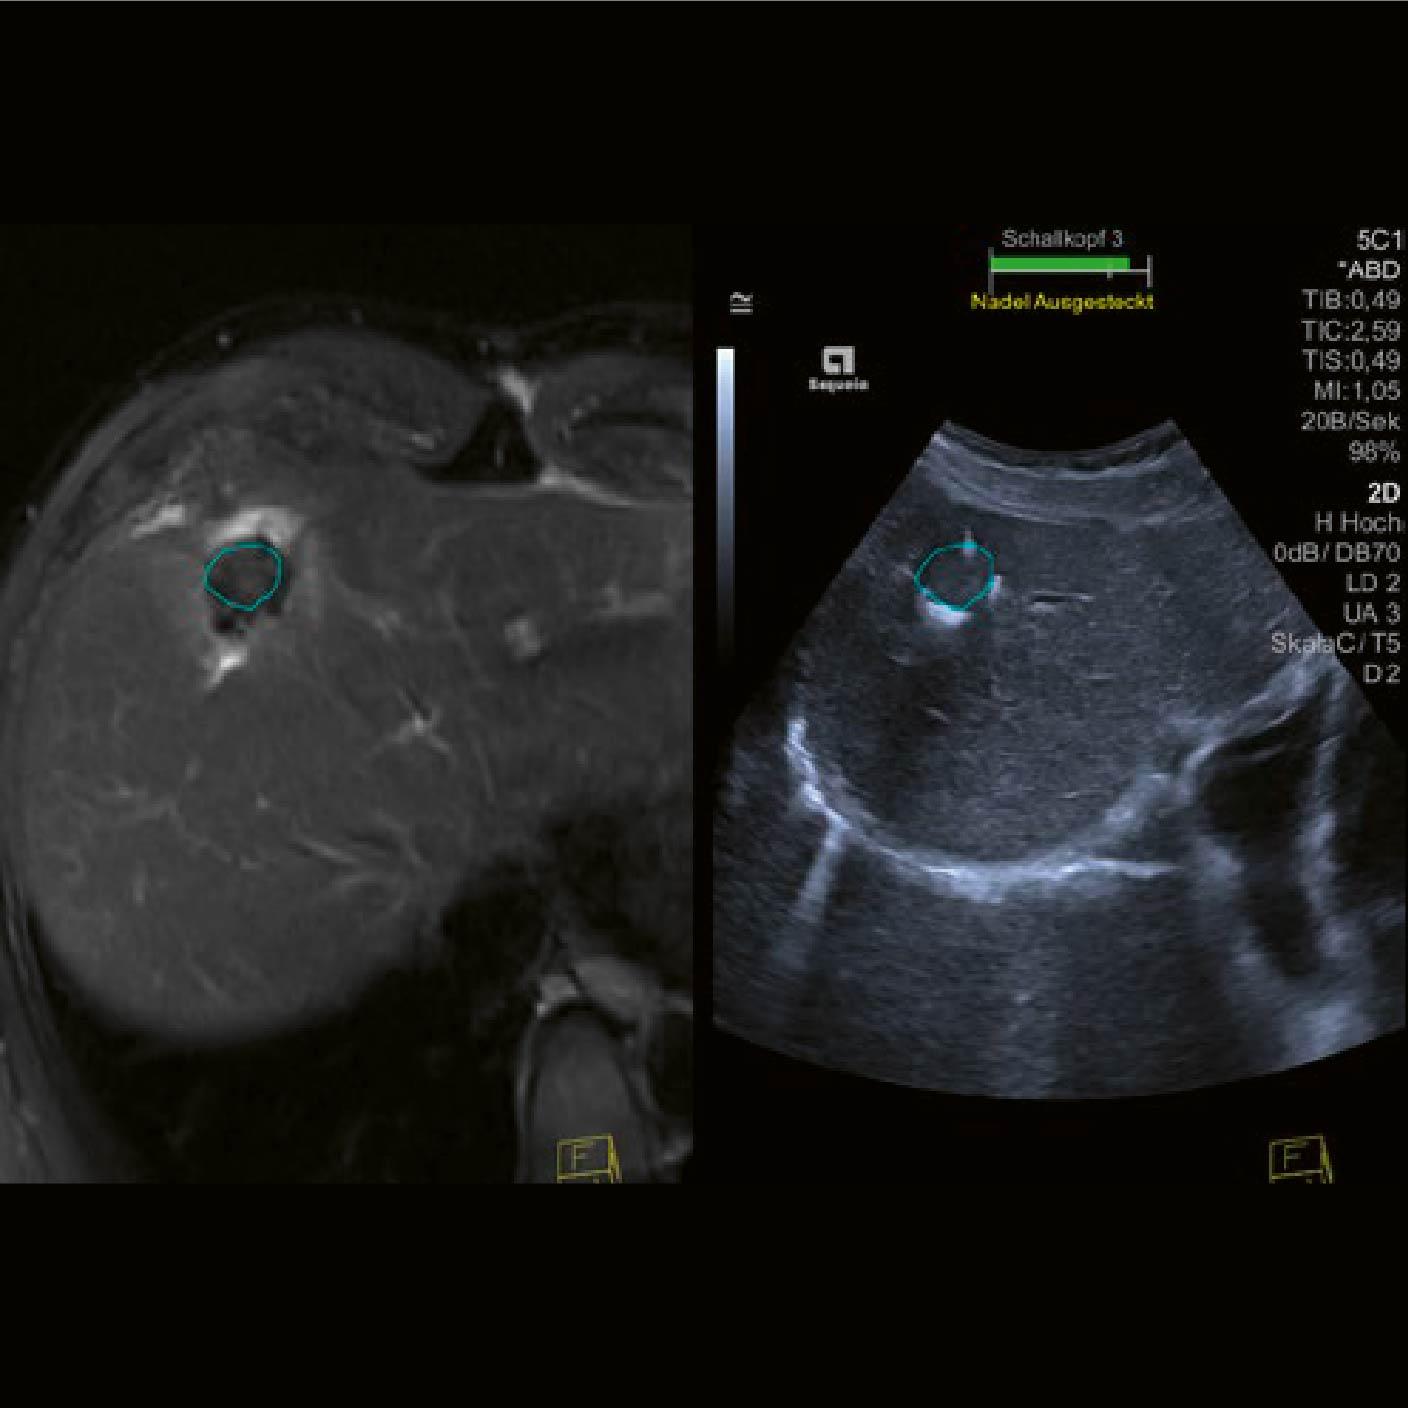

Las imágenes de la RM fueron cargadas en el sistema ACUSON Sequoia y se activó la tecnología de Fusión. Durante la fase de planificación, se utilizó segmentación automática para alinear de manera eficaz el área tratada [círculo azul Fig. 2].